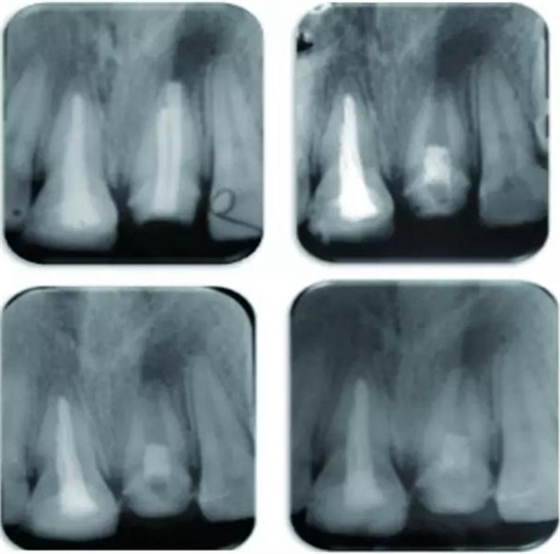

例為兩名年齡分別為26歲和12歲的男性患者,各有一顆恒牙(牙位分別為21與35)因患有根管治療后持續(xù)性根尖周炎而需進行再治療。用Carvene 牙膠溶解劑和ProTaper普通旋轉式再治療根管銼去除患牙根管內充填的牙膠,接著進一步用旋轉再治療銼和大量次氯酸鈉對根管進行化學機械法清理,然后用Metapaste 干燥根管。對21和35兩患牙進行牙髓再生術治療。將根尖周的出血引入消毒后的根管內,用礦物三氧化物聚合物(MTA)填料覆蓋血塊,根管口修復材料填充。

結果為,兩患牙分別在隨訪13個月及14個月時表現(xiàn)出根尖周炎的臨床恢復體征和/或癥狀。21患牙顯示出根管變窄以及根尖部硬組織沉積而形成根尖封閉。

圖 21治療全過程,圖A 為治療前根尖片,圖B 為術后根尖片,圖C 顯示治療7 個月后根尖陰影縮小,圖D顯示治療后13個月根管口變窄